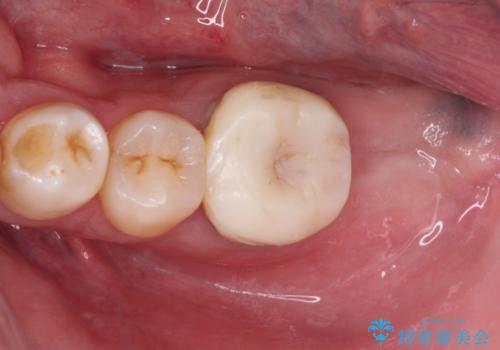

- 近医にて奥歯の抜歯が必要と言われたとのことで来院された患者様です。

診査の結果、歯が破折しており、抜歯が必要な状態でした。

最後方歯であるため、入れ歯かインプラントかどちらかの補綴治療を行うこととなりますが、ご希望によりインプラント補綴治療を行うこととしました。

インプラントにはストローマン社のSLActiveを使用し、埋入から補綴までおよそ3か月と、短期間で治療を進めることができました。